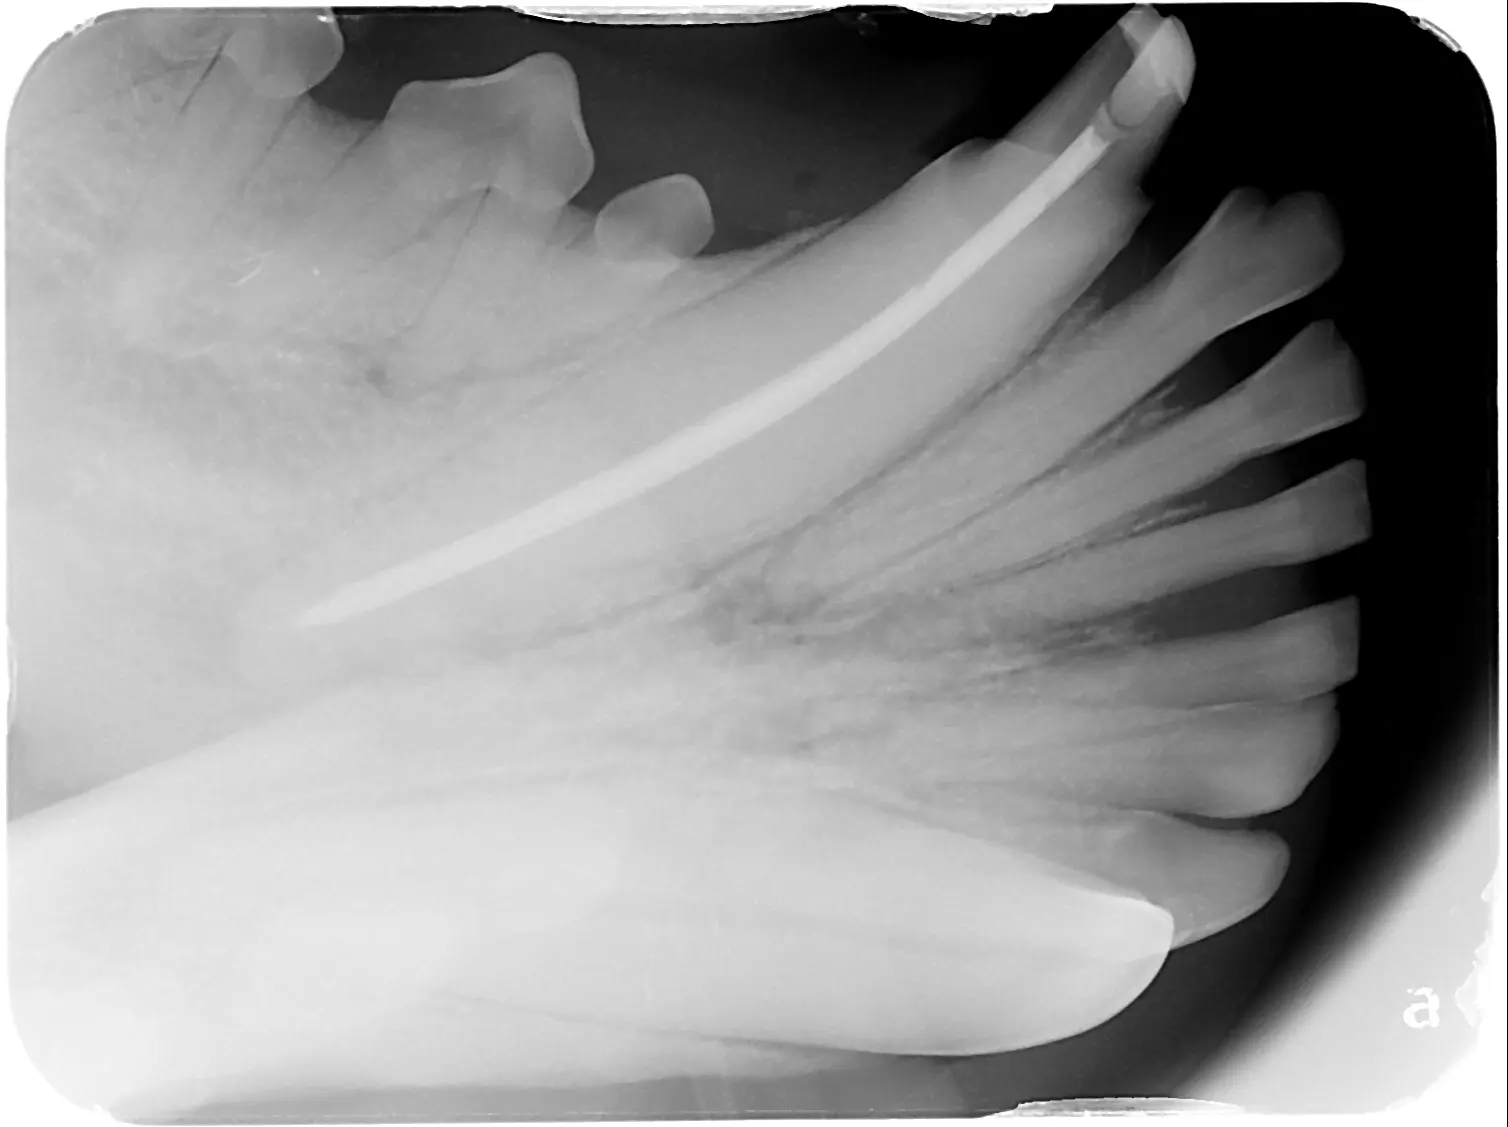

When it comes to your petโs dental health, what you see on the surface doesn’t tell the whole story. Many

Pet Dental X-Rays: Why Theyโre Essential Before a Cleaning Read Post ยป